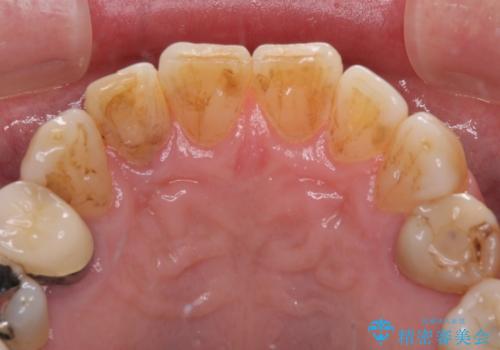

憧れの白い歯に 全顎セラミック治療

- 60歳を越え、黄ばんだ前歯をセラミッククラウンできれいな口元にしたいとのことで来院された患者様です。

診察したところ、前歯は反対咬合であり、その影響で抜歯が必要な奥歯があることが分かりました。

抜歯が必要な奥歯は、インプラント並びにブリッジにより補綴を行い、上下前歯は反対咬合を改善させるように補綴治療を行うこととしました。

健全な歯を削ってセラミッククラウンに置き換えることは、本来避けるべき治療と考えますが、今回は①患者様が60歳を越えていること、②要改善の咬合により抜歯が必要な奥歯があること、③反対咬合の前歯改善の手段としてセラミック治療が選択肢にあることなどから、全顎的なセラミック治療を行うこととしました。